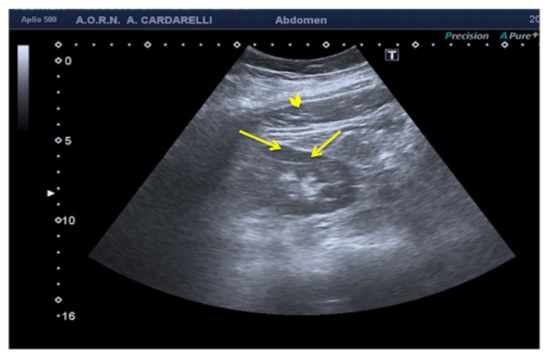

3.1.5. Reverberation Artifacts

Because the US beam is reflected back and forth several times between two highly reflective parallel surfaces (“reverberates”), the US transducer interprets the reflected echoes as happening at deeper structures because they take longer to return to the transducer (Figure 10 and Figure 11) [3]. This very common mistake can be easily solved with a change of the angle of insonation in order to avoid the reverberation between strong parallel reflectors [5,6].

Figure 11. Coronal images of the right kidney. A reverberation artifact from strong echoes of the abdominal wall (arrowhead) projects over the lateral margin of the kidney, mimicking the presence of a subcapsular hematoma (arrows).